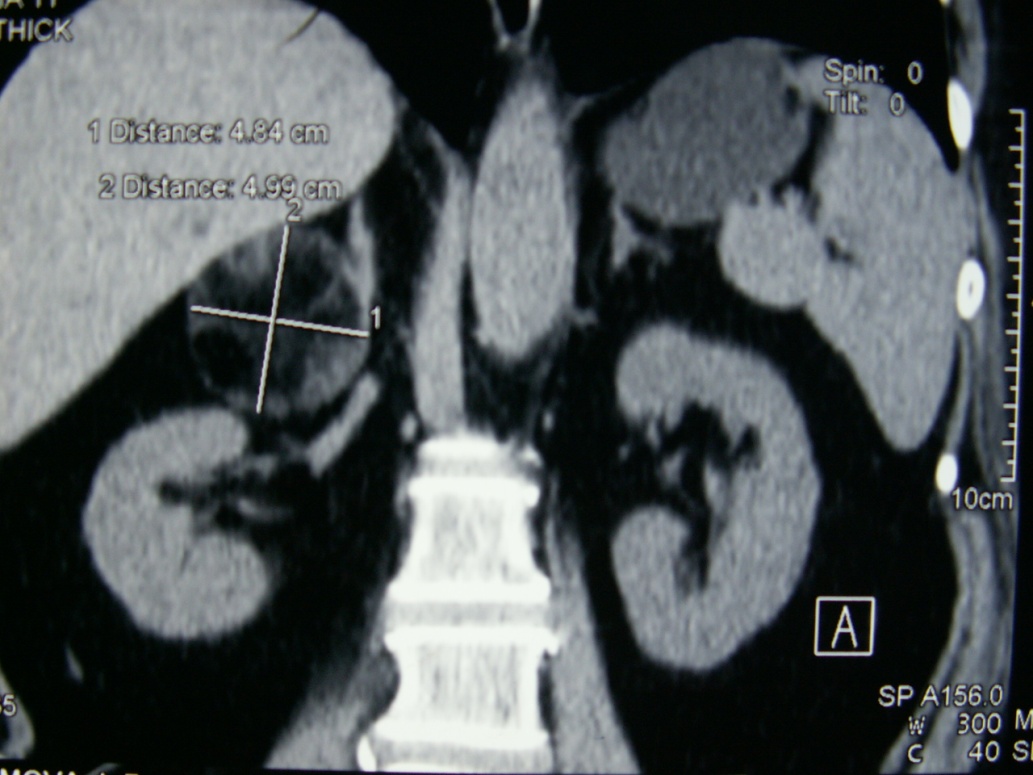

Source: Cancer Urology; Том 13, № 2 (2017); 121-123 ; Онкоурология; Том 13, № 2 (2017); 121-123 ; 1996-1812 ; 1726-9776 ; 10.17650/1726-9776-2017-13-2

Subject Terms: лапароскопическая адреналэктомия, adrenal myelolipoma, laparoscopic adrenalectomy, миелолипома надпочечника

Relation: https://oncourology.abvpress.ru/oncur/article/view/654/667; https://oncourology.abvpress.ru/oncur/article/downloadSuppFile/654/442; https://oncourology.abvpress.ru/oncur/article/downloadSuppFile/654/443; https://oncourology.abvpress.ru/oncur/article/downloadSuppFile/654/444; https://oncourology.abvpress.ru/oncur/article/downloadSuppFile/654/445; https://oncourology.abvpress.ru/oncur/article/downloadSuppFile/654/446; Dan D., Bahadursingh S., Harinaran S. et al. Extra-adrenal perirenal myelolipoma. A case report and review literature. G Chir 2012;33(3);62–5. DOI:10.11138/2012.33.5.62-5. PMID: 22525547.; Sanders R., Bissada N., Curry N., Gordon B. Clinical spectrum of adrenal myelolipoma: analysis of 8 tumors in 7 patients. J Urol 1995;153(6):1791–3. DOI:10.4103/0970-1591.152807. PMID: 7752318.; Han M., Burnett A.L., Fishman E.K., Marshall F.F. The natural history and treatment of adrenal myelolipoma. J Urol 1997;157(4):1213–6. PMID: 9120904.; Bhansali A., Dash R.J., Singh S.K. et al. Adrenal myelolipoma: profile of six patients with a brief review of literature. Int J Endocrinol Metab 2003;1:33–40.; Clark O.H., Duh Q.Y., Perriet N.D., Jahan T.M. Endocrine tumors. Atlas of Clinical Oncology. BC Decker, 2003.; Бондаренко В.О., Дэпюи Т.И., Бондаренко Е.В. и др. Миелолипома надпочечников. Эндокринная хирургия 2013;(4):25–38. [Bondarenko V.O., Depyui T.I., Bondarenko E.V. et al. Adrenal myelolipoma. Endokrinnaya khirurgiya = Endocrine Surgery 2013;(4):25–38. (In Russ.)]. DOI:10.14341/serg2013425-38.; Lin P., Yang F. Bilateral giant adrenal myelolipomas: a case report and literature review. Chin J Radiol 2008;33:261–4.; Wrightson W.R., Hahm T.X., Hutchinson J.R., Cheadle W. Bilateral giant adrenal myelolipomas: a case report. Am Surg 2002;68(6):588–9. DOI:10.1159/000078383. PMID: 12079144.; Fernandes G.C., Gupta R.K., Kandalkar B.M. Giant adrenal myelolipoma. Indian J Pathol Microbiol 2010;53(2):325–6. DOI:10.4103/0377-4929.64314. PMID: 20551546.; Chung H., Luo F., Wu T., Tsai Y. Adrenal myelolipoma with spontaneous hemorrhage. Urol Sci 2010;21(3):152–4.; Chakrabati I., Ghosh N., Das V. Giant adrenal myelolipoma with hemorrhage masquerading as retroperitoneal sarcoma. J Midlife Health 2012;3(1):42–4. DOI:10.4103/0976-7800.98818. PMID: 22923980.; Gerson G., Bêco M. Giant retroperitoneal myelolipoma: case report and literature review. J Bras Patol Med Lab 2015:48–51. DOI:10.5935/1676-2444.20150010.; Al Hatthi B., Riaz M.M., Al Khalaf A.H. et al. Adrenal myelolipoma a rare benign tumour managed laparoscopically: report of two cases. J Minim Access Surg 2009;5(4):118–20. DOI:10.4103/0972-9941.59312. PMID: 20407573.; https://oncourology.abvpress.ru/oncur/article/view/654